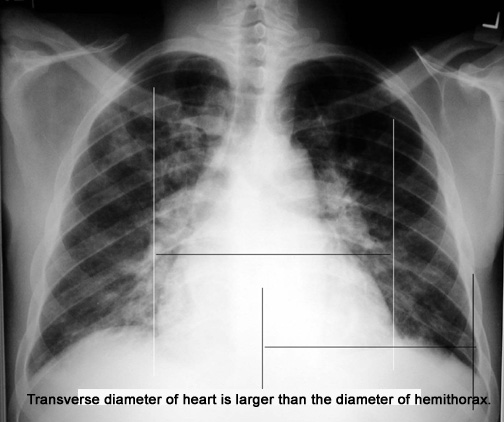

Cardiomegaly